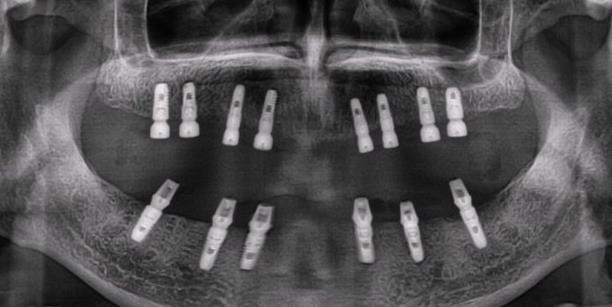

采用全口種植牙修複的情況的,特別是種植全口24顆牙齒的情況是比較少的,一來是價(jia) 格非常貴,二來是工程量比較大,修複起來比較費時費力。但是如果真的做滿口種植牙,種植24顆牙,需要多少錢...

愛康健口腔醫院醫生表示,能不能做全口牙種植是需要先到醫院檢查後,醫生判斷符合適應症要求才可以的。還有隻有先確定每一顆牙齒的價(jia) 格才能確定24顆牙齒的總價(jia) 格,目前市場上種植牙的平均價(jia) 格在5千到1萬(wan) 左右,所以計算下來,總的價(jia) 格應該在十幾萬(wan) 到幾十萬(wan) 左右。